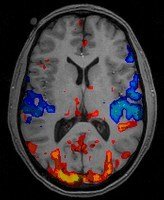

Predicting the brain's response to images using fMRI